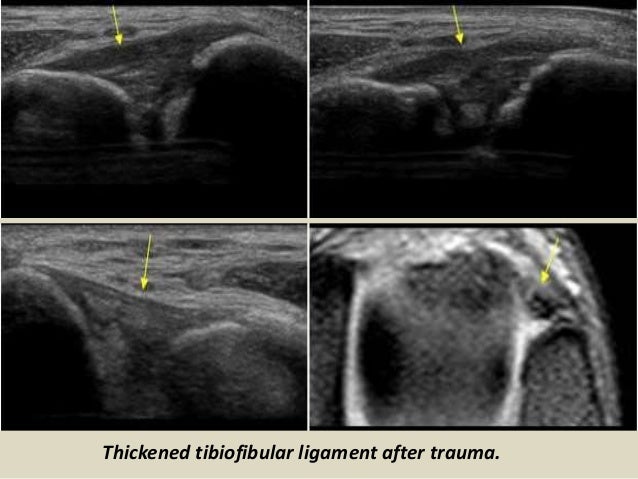

Thickened tibiofibular ligament after trauma.

66. 66. Thickened tibiofibular ligament after trauma.